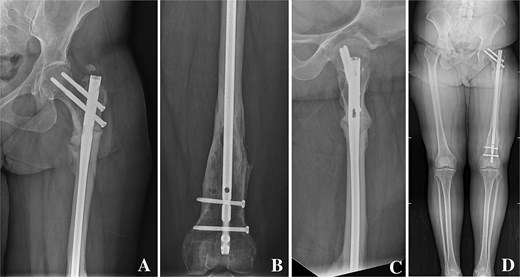

On clinical examination, the left thigh was swollen and ecchymotic with visible deformity. Passive and active range of motion at the hip and knee was markedly restricted due to pain. Distal neurovascular function was intact. All laboratory investigations were negative or normal. Radiographs of the femur, hip, and knee revealed a hypertrophic malunion at the distal femur with a proximal periprosthetic fracture and an intramedullary nail inserted (Fig. 1). A preoperative non-contrast computerized tomography (CT) scan of the left thigh confirmed an old distal femoral fracture with in situ fixation and extensive hypertrophic callus. Multiple small free bone fragments were seen in the distal thigh. The hardware extended beyond the distal and medial cortical margins, with screws also breaching the cortex. An oblique fracture line was noted proximally adjacent to the proximal screw, without displacement. No soft tissue hematoma or joint effusions were identified (Fig. 2). The patient was admitted for surgical management. Revision antegrade nailing was performed intraoperatively. Upon removal of the retrograde nail it was confirmed to be an antegrade construct (Fig. 3). A correctly sized antegrade femoral nail was inserted via the proximal entry point under fluoroscopic guidance. Postoperative imaging demonstrated satisfactory alignment and stable fixation. At follow-up, the patient reported improved mobility and reduced pain. Radiographs showed signs of progressive healing. No signs of infection, implant loosening, or neurovascular compromise were observed (Fig. 4).

(A, B) Anteroposterior radiographs of the proximal and distal femur showing a correctly positioned antegrade femoral nail inserted via the appropriate proximal entry site. (C) Lateral radiograph of the femur showing stable fixation with appropriate screw placement and no evidence of cortical breach. (D) Scanography of the lower limbs demonstrating restored mechanical alignment.